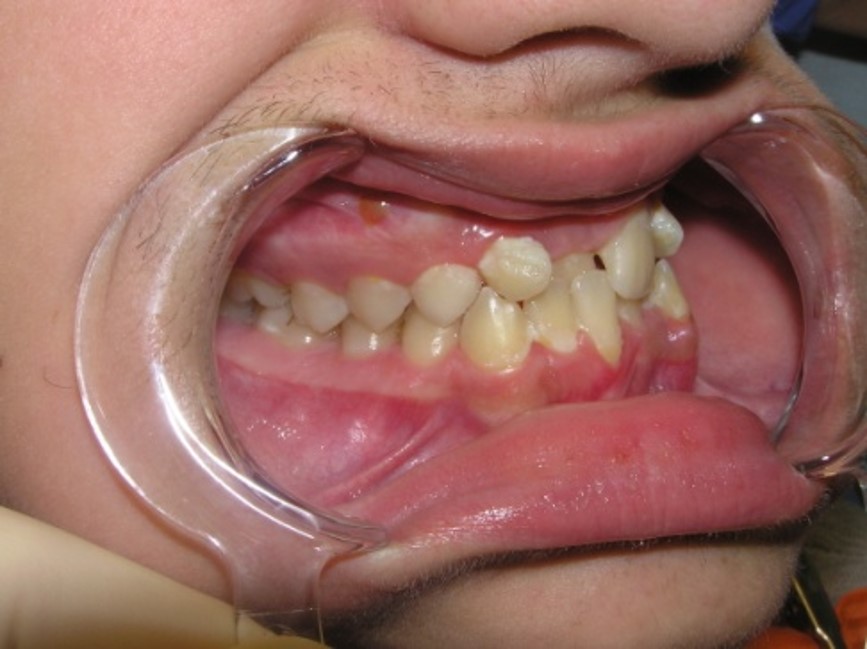

Sysoev N. P. (1975) proposed a

classification of the palatal position of the frontal teeth and identified 4

forms:

Form 1 – palatal position of the

frontal teeth when there is space in the dental arch of the upper jaw. Occurs in

42.4%

Form 2 – palatal position of the

frontal teeth with lack of space in the dental arch as result of the upper jaw

frontal area underdevelopment. Occurs in 29.6%

Form 3 – palatal position of the

frontal teeth, which is combined with protrusion of the lower jaw frontal teeth.

Occurs in 16.89% of cases.

Form 4 – palatal position of the

upper jaw frontal teeth with a lower teeth crowding. Occurs in 11.2%